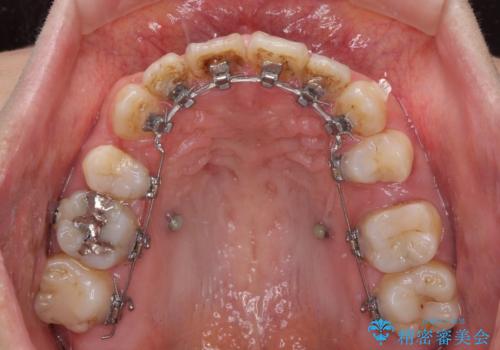

- ハーフリンガル

- 2年8ヶ月

開咬の改善には舌突出癖を改善するためのトレーニングが必要ですが、しっかりと行っていただき、想定よりも早い期間で治療を終えることができました。